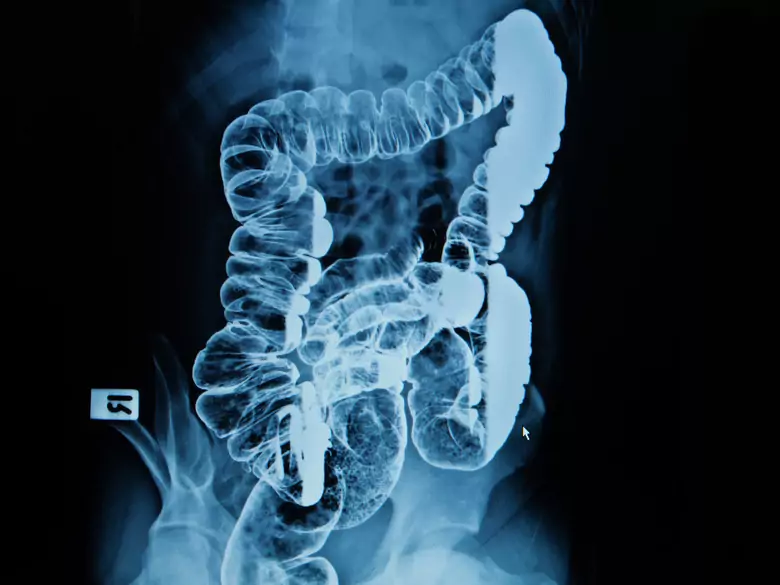

Angiodysplazja jelitowa - przyczyny, objawy, diagnoza, leczenie

Jelita